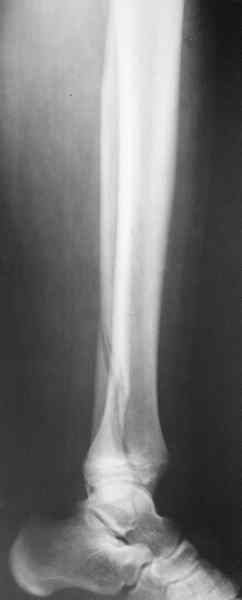

Есть смысл начать с наложения дистрактора голень-стопа. Лигаментотаксис может очень существенно помочь с репозицией. При переломе малоберцовой кости этот подход позволяет не тратить время на ее остеосинтез. Больших участков импрессии суставной поверхности не видно, перелом больше по типу раскалывания. Это делает возможной полностью закрытую репозицию с фиксацией либо аппаратом, либо компрессирующими винтами и аппаратом, либо пластиной малоинвазивно.

1 - перелом закрытый;

2 - соотношение осей голени и стопы практически идеальное;

И какой смысл переводить закрытый в открытый, подвергать операционным рискам пациента с ГБ в 60 лет? Тем более, что после операции наступать на ногу ему никто не разрешит минимум 3 месяца. Моё мнение - только консервативно и под регулярным контролем и дозированным ЛФК, причем движения в суставе начинать не познее конца 6-ой недели, а лучше с 5-ой.

Не проводить остеосинез малоберцовой кости в случае ее перелома (при сочетании с пилоном)-считаю ошибкой! На мой взгляд-имперссия очевидна и значительна. Я за открытую репозицию!

Напомню, речь идет не о переломе лодыжек, тут механизм травмы другой, и малоберцовая может вообще быть целой при тяжелых разрушениях дистального конца большеберцовой.

На мой взгляд-имперссия очевидна и

значительна. Я за открытую репозицию!

Если несложно, в графическом редакторе выделите pls то, что Вы полагаете участками импрессии.